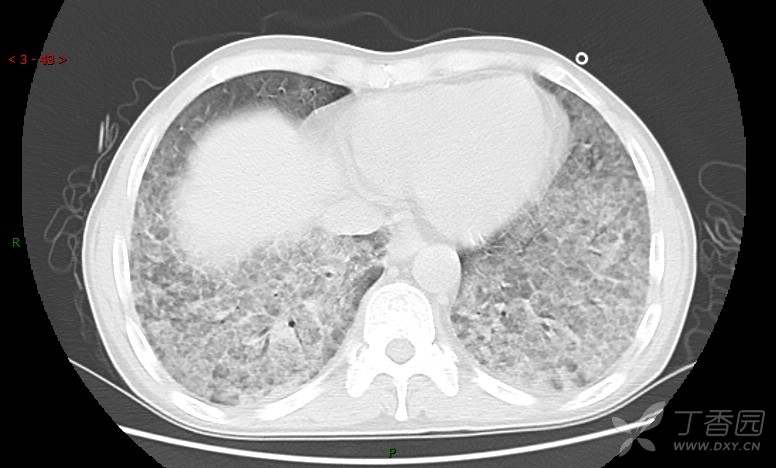

地图+铺路石征=PAP?那升高的CEA怎么说(病例3连发,附其他2例链接)

原帖名:刚入手的病例,看着都憋得慌,有PET/CT,请讨论(病例3连发,附其他2例链接)

患者男,42岁,咳嗽半年余,加重伴憋喘2月余。

患者半年余前无明显诱因出现间断咳嗽,干咳为主,偶咳少量黄白痰,剧烈咳嗽或运动后可出现轻度憋喘,无高热、脓臭痰,无胸痛、咯血及晕厥,无低热乏力及盗汗,无心前区压榨感及夜间阵发性呼吸困难,初未在意,未予正规诊治。2月余前患者自觉上述症状较前加重,咳嗽、憋喘明显,黄白色粘痰略有增多,伴有发热,热前伴有畏寒、寒战,体温最高达38.9℃,先后就诊多家医院,入住重症监护室,未行气管插管,考虑“重症肺炎”,给予“美罗培南、复方磺胺甲噁唑”等药物抗感染,“卡泊芬净”抗真菌,并给予“甲泼尼龙”等药物治疗35天,经治疗后症状好转于2018-04-02出院。患者自出院后仅应用中药治疗(具体不详),并给予家庭氧疗,平素仍有间断咳嗽,咳少量黄白色粘痰,活动后憋喘明显,活动耐量差,以卧床为主。

肺内弥漫性网状结节影,PET-CT却无阳性病灶,这是?(附其他2例链接)